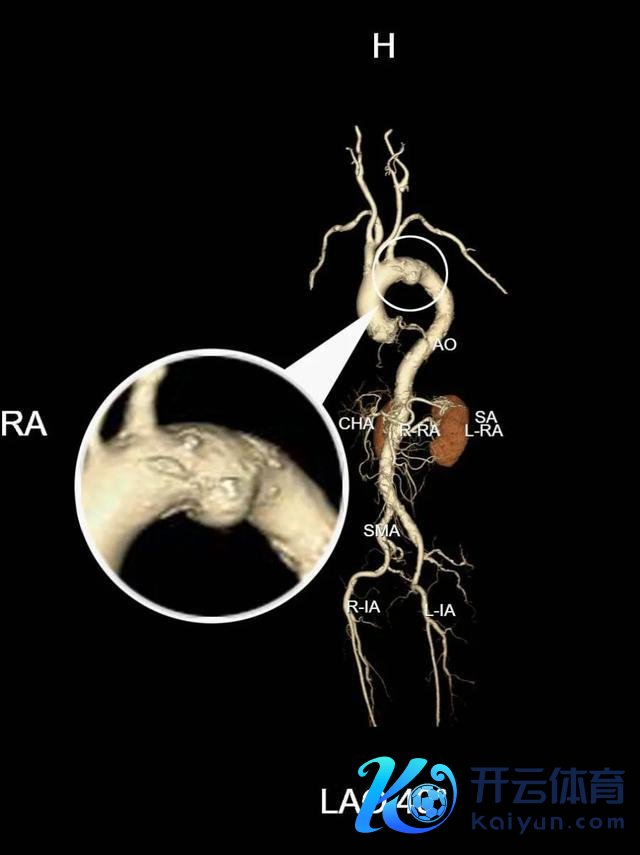

近日,吴爷爷因为慢性支气管炎急性发作,到奉城病院呼吸科入院诊治,入院时期进行CT查验,CT文告披露:主动脉弓部动脉瘤可能?

复查文告披露主动脉弓动脉瘤伴血栓酿成可能

明确诊断后,宋主任立即关系九院血管外科大家刘光主任,为吴爷爷制定诊治决策,由于基础疾病较多,随即运行MDT多学科诊治样式,在奉城病院血管外科的引颈下,呼吸科、麻醉科、DSA等科室全力联接。